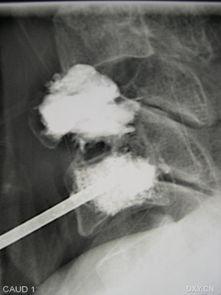

3. 注入骨水泥:通过穿刺针,医生会将一种特殊的骨水泥注入到压缩的椎体中。这种骨水泥具有很高的强度,可以迅速凝固,为椎体提供支撑。

4. 拔针:手术完成后,医生会拔出穿刺针,并为你贴上创可贴。整个过程就像是在城堡的墙壁上加固了一层钢筋,既美观又坚固。